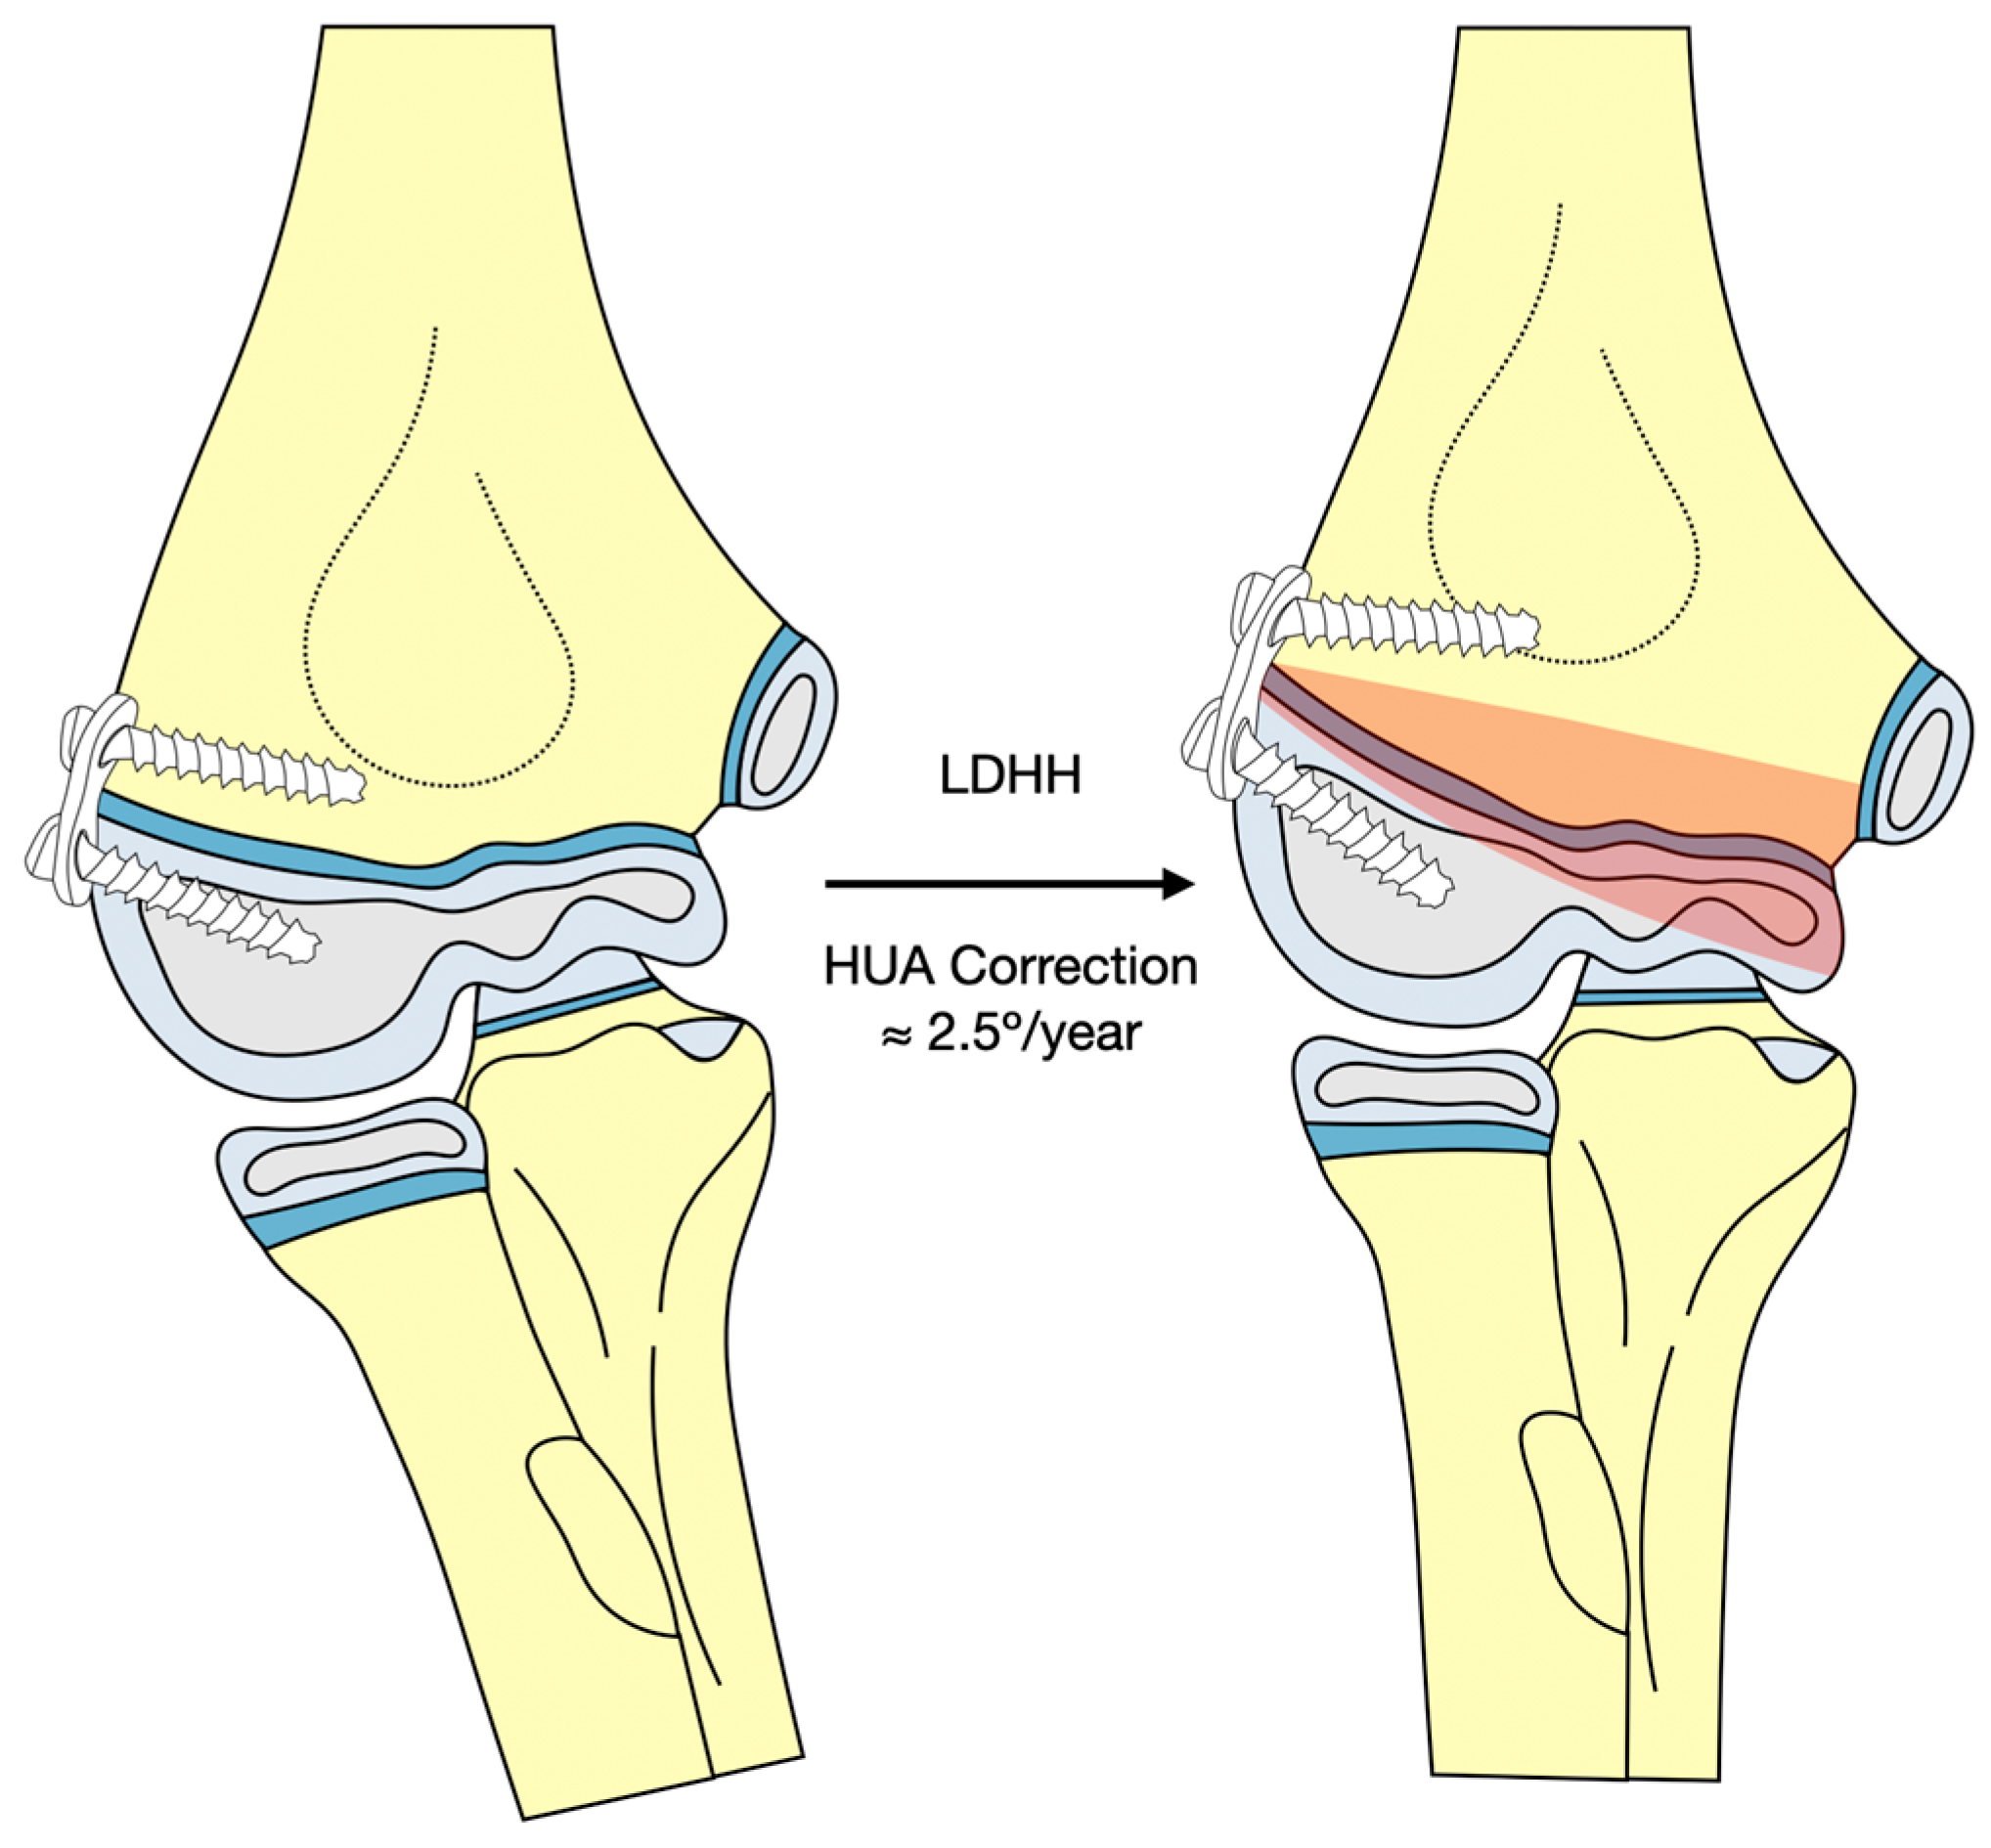

- Verka, P.S. A novel minimally invasive method in pediatric cubitus varus deformity, distal lateral humerus hemiepiphysiodesis: A case report. J. Pediatr. Neurol. Disord. 2021, 4, 1–2. [Google Scholar]

- Soldado, F.; Diaz-Gallardo, P.; Cherqaoui, A.; Nguyen, T.-Q.; Romero-Larrauri, P.; Knorr, J. Unsuccessful mid-term results for distal humeral hemiepiphysiodesis to treat cubitus varus deformity in young children. J. Pediatr. Orthop. B 2022, 31, 431–433. [Google Scholar] [CrossRef]